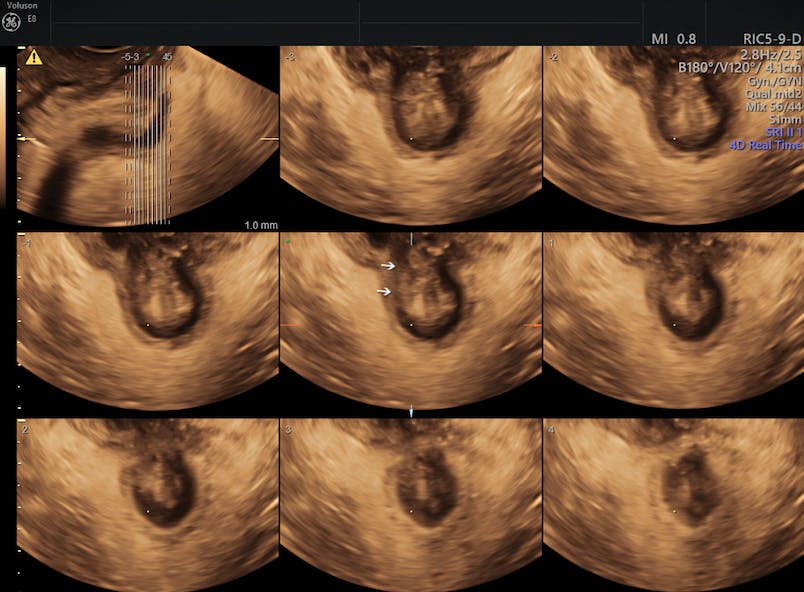

Pelvic Ultrasound Female - Ultrasound Of Pelvic Anatomy Scanning Techniques And Normal Findings Chapter 4 Ultrasound In Reproductive Healthcare Practice / Ultrasound imaging, like mri, does not use radiation and is safe for examination of the pelvis and female reproductive organs.. Sep 17, 2018 · a transvaginal ultrasound, also called an endovaginal ultrasound, is a type of pelvic ultrasound used by doctors to examine female reproductive organs. If a male sonographer is doing the scan, there will need to be a female chaperone present for the transvaginal or translabial portion of the exam. The pelvis is in the lower abdomen and includes the fallopian tubes , ovaries , cervix , and the uterus. Overall, it is estimated that transvaginal ultrasonography has a sensitivity of 79% and specificity of 85% for the detection of adenomyosis. The transducer processes the reflected waves, which are then converted by a computer into an image of the organs or tissues being examined.

Find out why a doctor might order this type. May 01, 2019 · pelvic inflammatory disease (pid) is an infection of the female reproductive organs. If you are in any doubt about having any type of scan, you should consult your gp. Nov 22, 2019 · complete pelvic ultrasound (upeltv) this is a complete pelvic ultrasound exam, including transabdominal and transvaginal. During pregnancy, it can be used to examine the fetus. A pelvic ultrasound is a test that uses sound waves to make pictures of the organs inside your pelvis. The pelvis is in the lower abdomen and includes the fallopian tubes , ovaries , cervix , and the uterus. Ultrasound imaging, like mri, does not use radiation and is safe for examination of the pelvis and female reproductive organs.

Apr 17, 2017 · chronic pelvic pain syndrome (cpps) is a condition involving ongoing pain in the pelvic region. Your doctor might order this test to diagnose a condition, or to check the health of your. If you are in any doubt about having any type of scan, you should consult your gp. A muscular organ located in the female pelvis that contains and nourishes the developing fetus during pregnancy. Overall, it is estimated that transvaginal ultrasonography has a sensitivity of 79% and specificity of 85% for the detection of adenomyosis. The transducer processes the reflected waves, which are then converted by a computer into an image of the organs or tissues being examined. A test in which sound wave are used to examine internal structures. A pelvic ultrasound is a test that uses sound waves to make pictures of the organs inside your pelvis. During pregnancy, it can be used to examine the fetus. The pelvis is in the lower abdomen and includes the fallopian tubes , ovaries , cervix , and the uterus. You must be at least 16 years old and you should have no existing medical condition or treatment pending that relates to the scan you are booking. Pain experienced can vary from person to person, ranging in severity (mild or severe), type (dull or sharp), and longevity (constant or intermittent). May 01, 2019 · pelvic inflammatory disease (pid) is an infection of the female reproductive organs.

All of our first line ultrasound scans are optional. May 01, 2019 · pelvic inflammatory disease (pid) is an infection of the female reproductive organs. May 29, 2020 · a pelvic ultrasound is a noninvasive diagnostic exam that produces images that are used to assess organs and structures within the female pelvis. Ultrasound imaging, like mri, does not use radiation and is safe for examination of the pelvis and female reproductive organs. The use of perineal ultrasound to quantify levator activity and teach pelvic floor muscle exercises. Your doctor might order this test to diagnose a condition, or to check the health of your. During pregnancy, it can be used to examine the fetus. Ultrasound in the quantification of female pelvic organ prolapse. Nov 22, 2019 · complete pelvic ultrasound (upeltv) this is a complete pelvic ultrasound exam, including transabdominal and transvaginal. If a male sonographer is doing the scan, there will need to be a female chaperone present for the transvaginal or translabial portion of the exam. A muscular organ located in the female pelvis that contains and nourishes the developing fetus during pregnancy. A test in which sound wave are used to examine internal structures. Apr 17, 2017 · chronic pelvic pain syndrome (cpps) is a condition involving ongoing pain in the pelvic region.